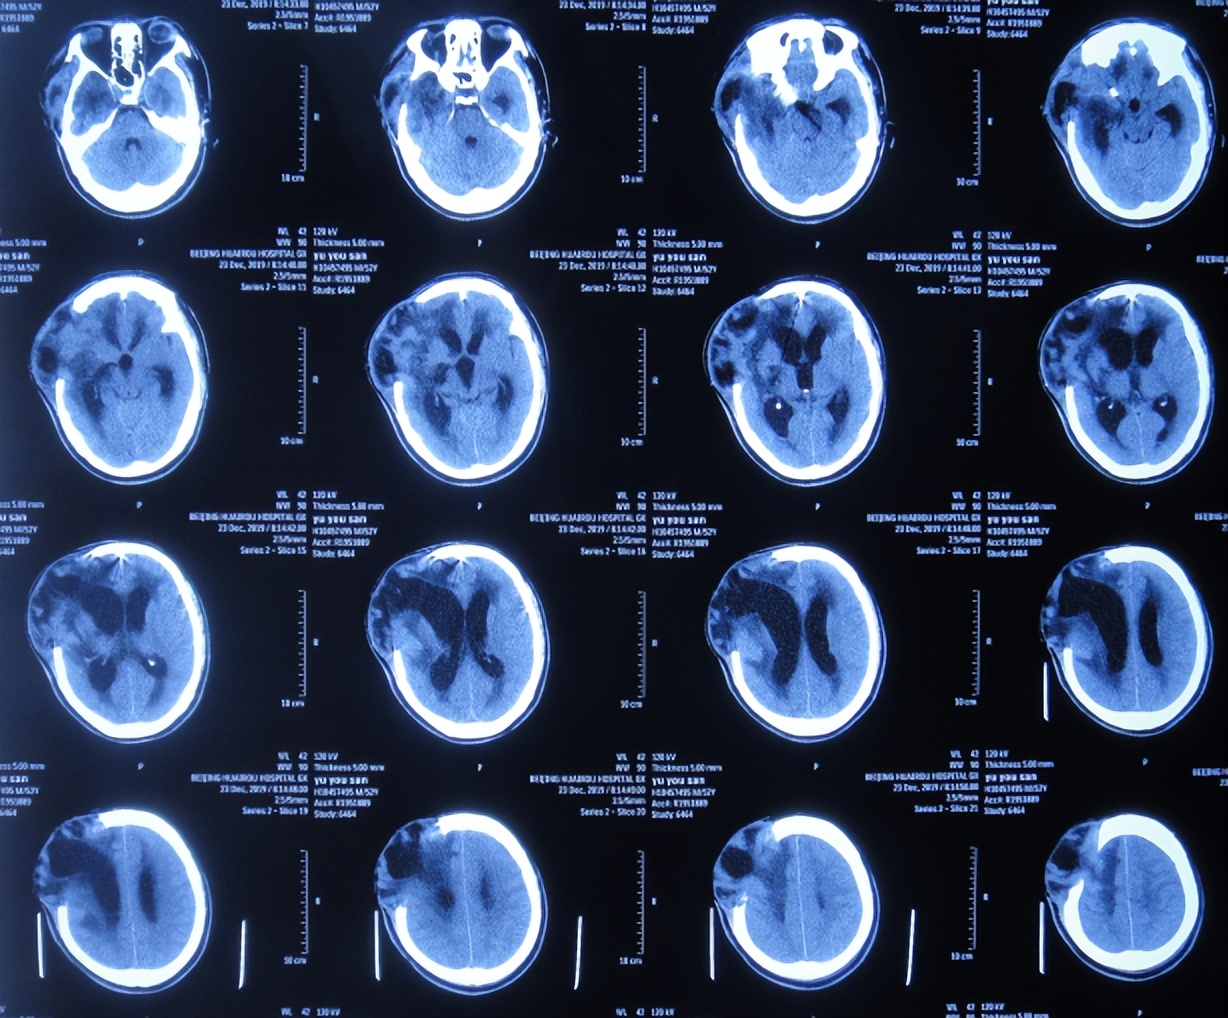

第2家医院治疗20天即2019年12月23日,期间间断给予腰穿治疗10余次,虽意识状态间断有所好转,但查头颅CT示脑室扩张严重,脑膨隆加重(图-4),继续给予腰穿治疗。

图-4:2019年12月23日头颅CT

但间断腰穿治疗大约42天即2020年1月17日,因脑室扩张,脑膨出进一步加重(图-5),给予腰大池引流术。

图-5:2020年1月17日头颅CT